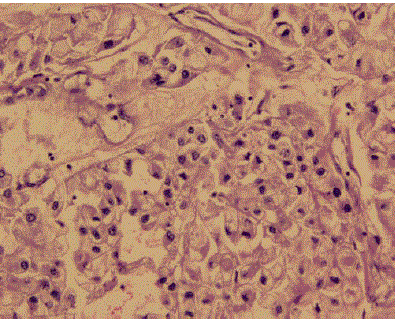

Figure 7. Renal-cell carcinoma. Hematoxylin-eosin (H&E) staining.